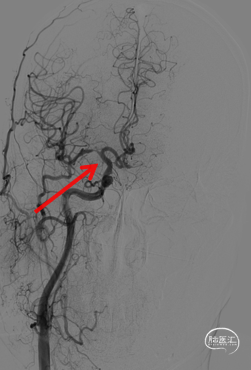

➢ DSA评估

造影显示左侧锁骨下动脉、右侧颈内动脉C5段、右侧大脑中动脉狭窄。左侧大脑前动脉A1段未见明确显示,左侧大脑后动脉局部管腔狭窄。

同轴下泥鳅导丝指引MPA多功能导管及长鞘至颈内动脉C1段,5F 通桥银蛇®颅内支持导管置于岩骨段,微导丝 300cm引导通桥白驹®颅内球囊扩张导管通过右侧大脑中动脉狭窄段。

通桥白驹®颅内球囊扩张,第1次球扩8 AMT(2.0*10mm)。

观察5分钟。

观察10分钟,第2次球扩(10 AMT),替罗非班5ml静推。

观察10分钟。

释放球扩支架(2.5*10mm)。

球扩支架后,造影显示仍有部分血管弹性回缩。

再次球囊扩张。

球扩后造影。